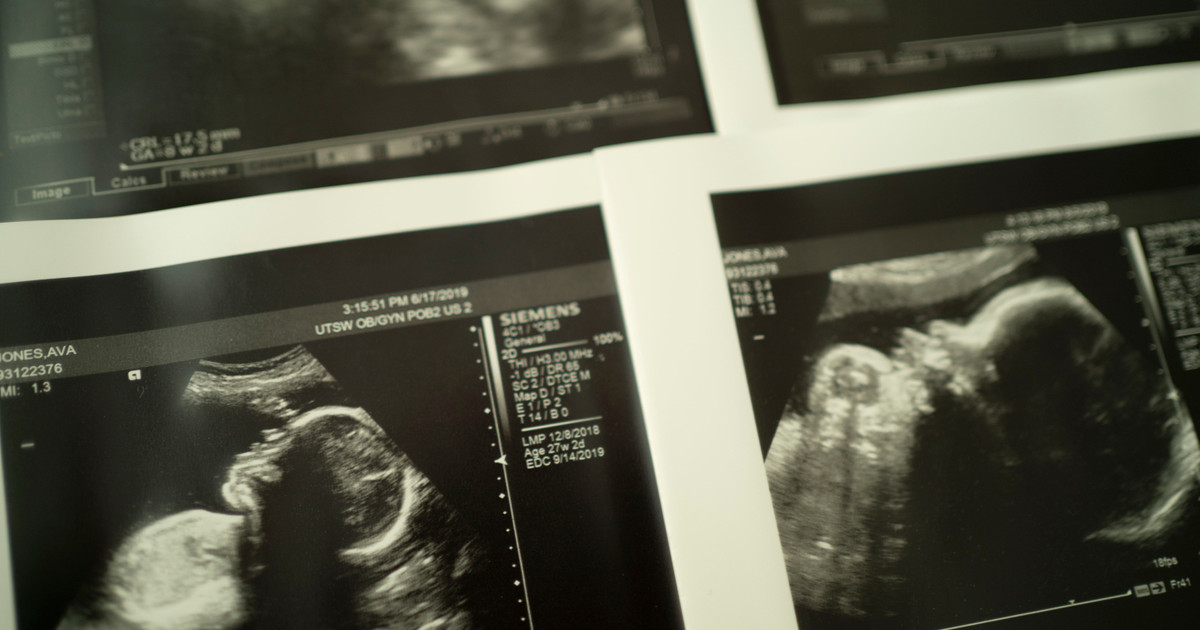

The primary focus of the consortium will be on predicting and preventing stillbirths. Research will explore various avenues, including understanding placental failure, assessing fetal movement, determining optimal delivery times, and utilizing advanced technologies like blood tests and ultrasounds. The teams also plan to investigate how electronic medical records and artificial intelligence can aid in early risk detection. Additionally, the consortium aims to address bereavement and mental health support for families who experience stillbirth.